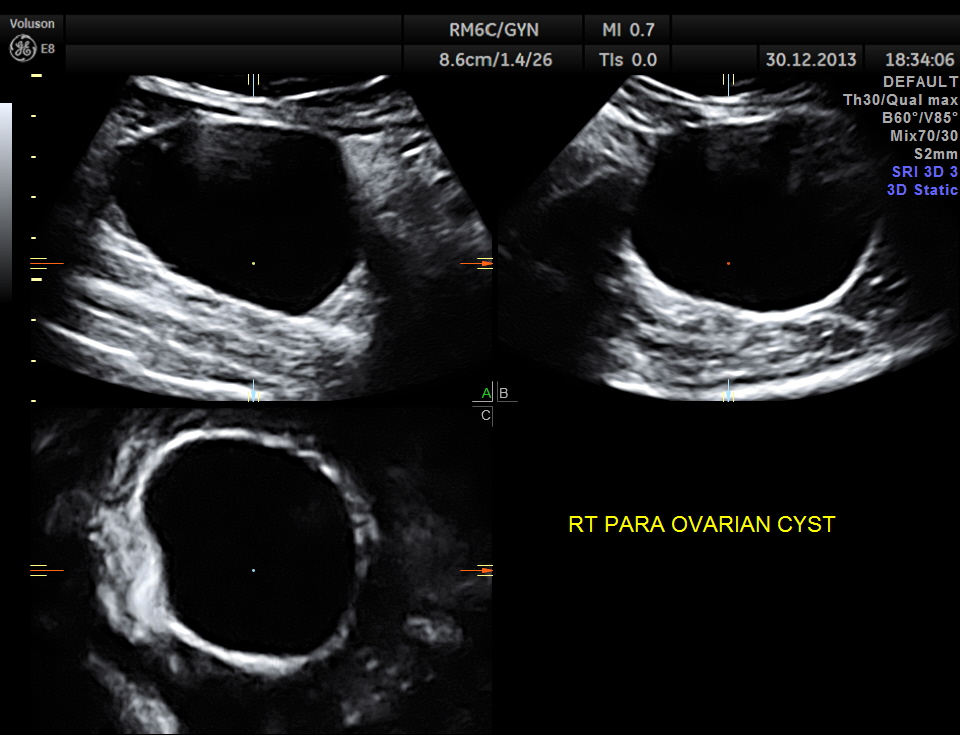

A para ovarian simple cyst was seen in the right adnexal region separate from the right ovary.

multi planar view is given below.